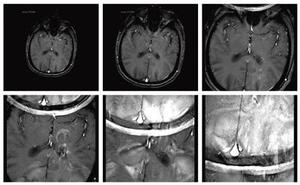

DWIやEPIシーケンスの問題点は,局所の磁化率による信号低下や歪みである。局所励起により,各軸のエンコードが低減できるため,磁化率の影響を受けやすい領域で拡散の定量評価がより一層向上すると考えられており,病変の検出を目的としたT2強調像とのフュージョン精度の向上(図6)や,FOV外からの体動によるアーチファクトの減少,体幹部のADCmap,fractional anisotropy(FA)mapの信頼性の向上(図7a,b),近年期待が高まっている体幹部の非造影パーフュージョン・フラクションのためのintra-voxel incoherent motion(IVIM)の高画質化, fMRIにおけるSNRの向上が期待されている。

図7